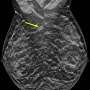

Study reveals alarming number of invasive breast cancers in younger womenStudy reveals alarming number of invasive breast cancers in younger women

A study of data from seven outpatient facilities in the New York region found that 20–24% of all the breast cancers diagnosed during an 11-year period were found in women aged 18 to 49, according to research being presented at the annual meeting of the Radiological Society of North America (RSNA).